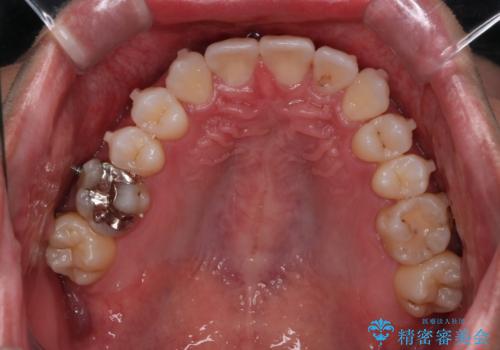

右上2番が欠損しているため、見た目と噛み合わせの両方のバランスを整えるために経過を追いながら必要な部位にゴム掛けをしました。

最終的に、見た目も噛み合わせも患者様に満足いただけました。

また矯正後、患者様の希望で

メタルインレーをセラミックインレーにやりかえさせていただき、さらに綺麗に仕上がりました。